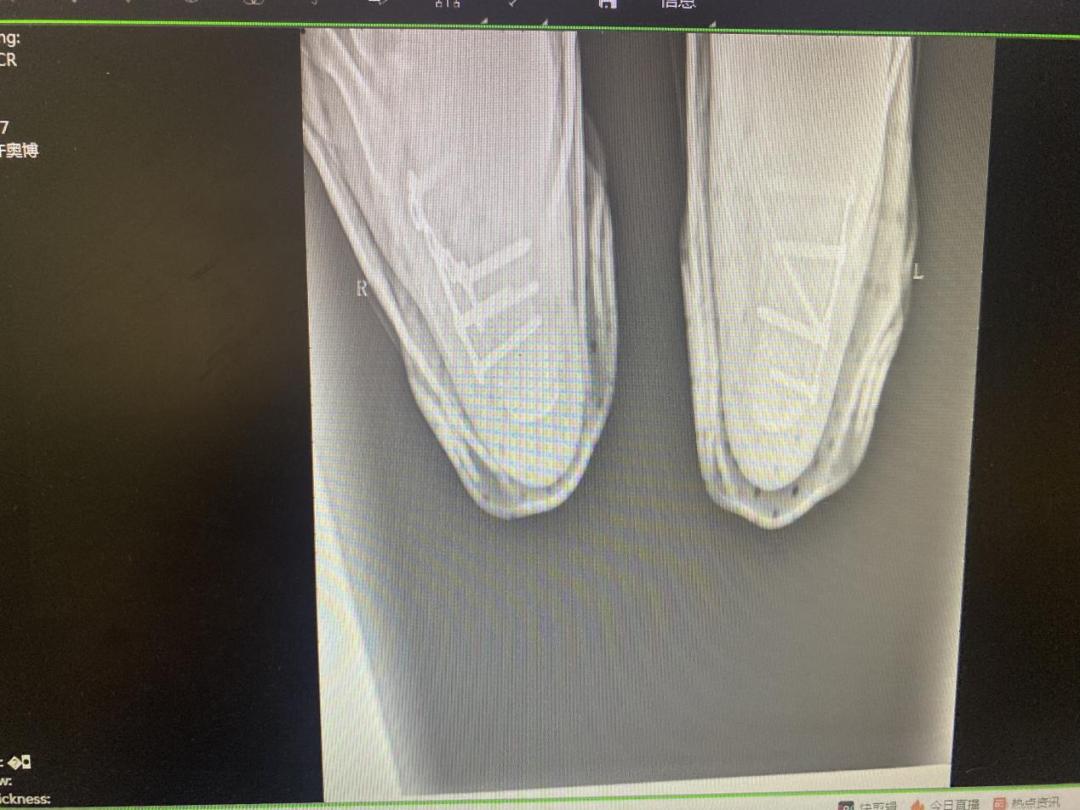

目前恢复照片